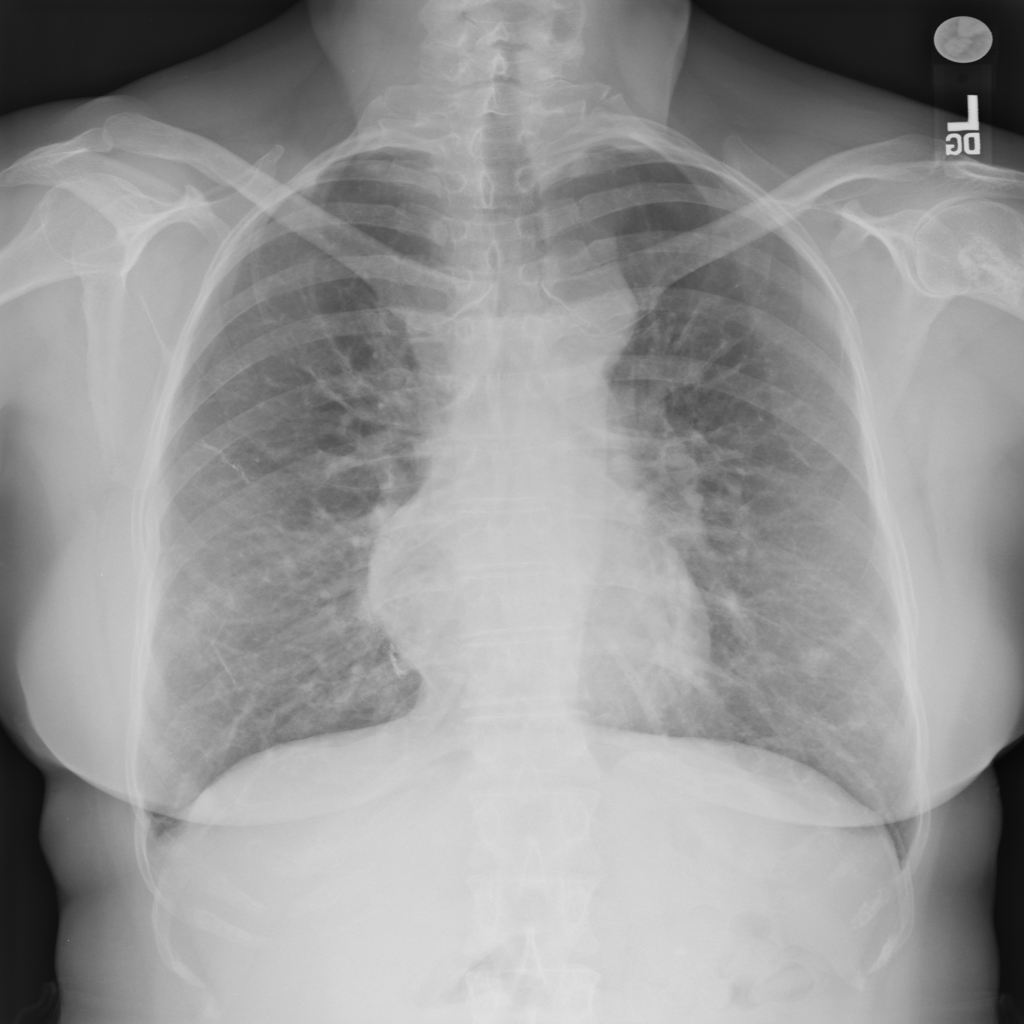

PAT-EEAA · IMG-002Nodule

PAT-EEAA · IMG-002

AP